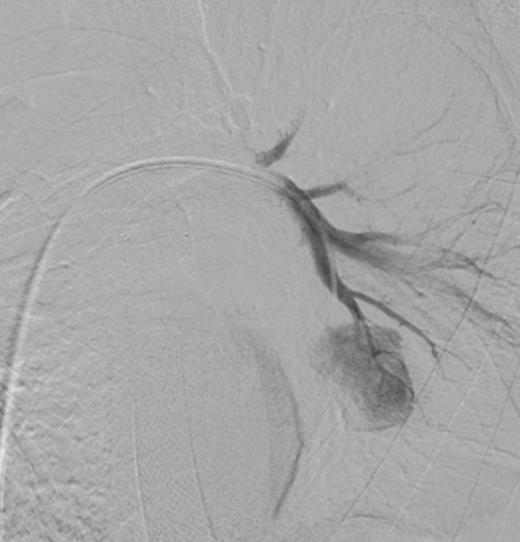

Coronal CT image in arterial phase demonstrating a 28mm diameter left lower lobe pulmonary artery aneurysm in association with a fluid collection

Three days later he presented with significant haemoptysis. A CT pulmonary angiogram (CTPA) demonstrated an increase in size of the PAA from 14mm to 28mm (Figure 1) diameter. A radiology opinion was sought and the patient transferred to the angio-suite for intervention.